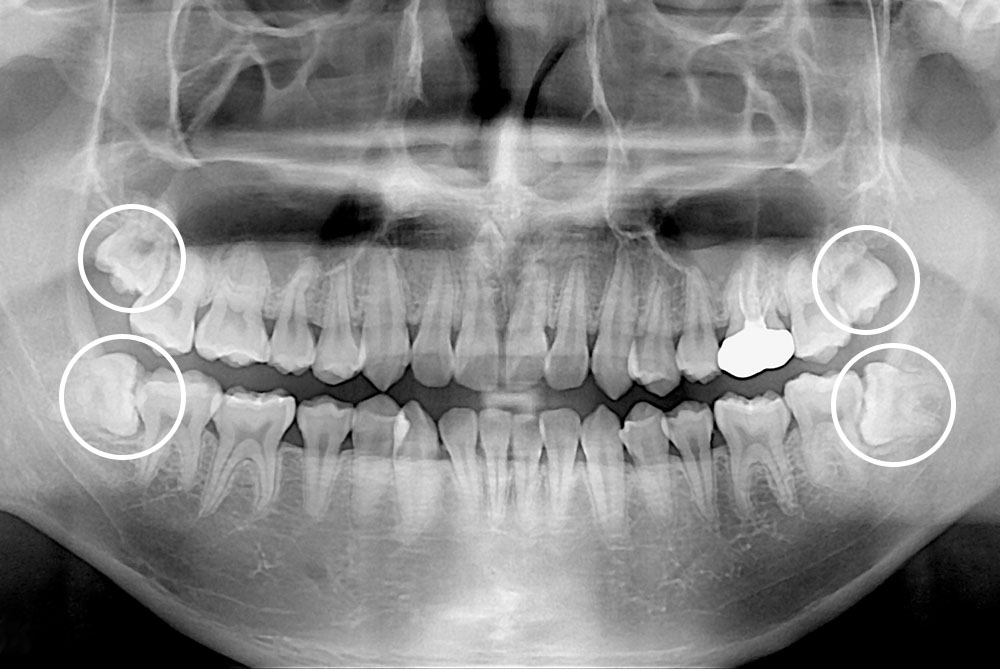

[사랑니] 매복 사랑니 발치

치료후 : 2020-12-18

세종치과는 구강악안면외과학 박사이신 원장님이 발치하는 치과입니다.